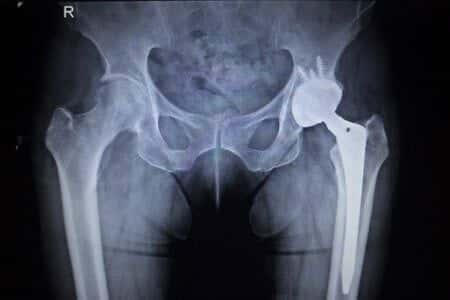

This case involves a patient who allegedly contracted a pulmonary infection following cardiothoracic surgery. The patient in question had undergone open heart surgery in order to treat a malformation in his aorta, during which he was placed on cardio-pulmonary bypass. In addition, the patient was also attached to a heater-cooler device in order to maintain his body temperature. It was claimed that a flaw in the design of the heater-cooler device allowed bacteria to enter the surgical site during the procedure.